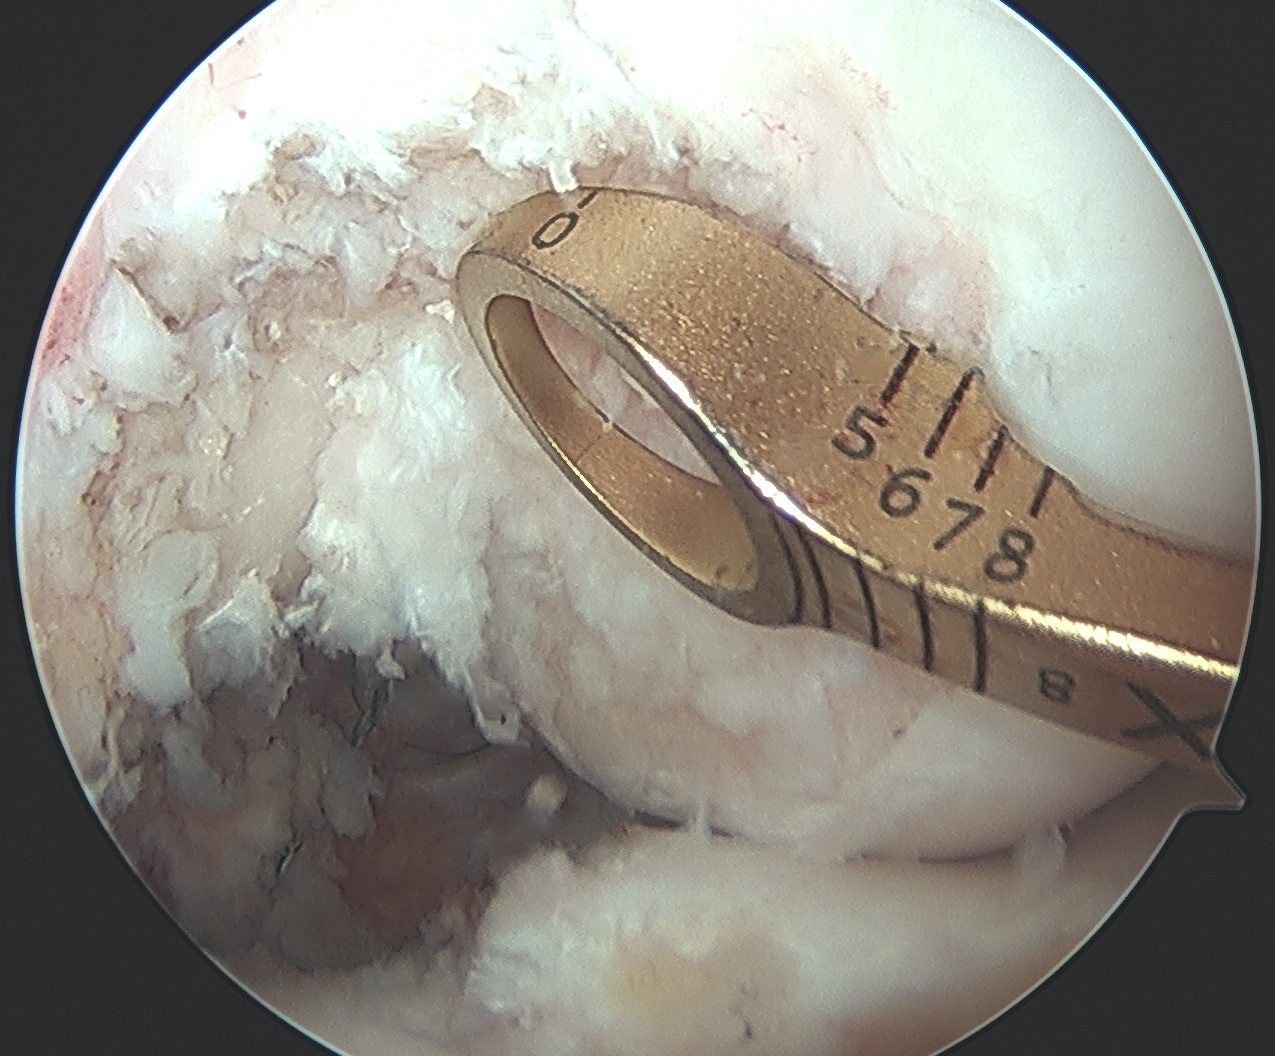

Drill MCL femoral tunnel

- 9 x 25 mm

- aim 40o anterior and 40o proximal to avoid PCL tunnel convergence

- insert bony plug and fix with a 7 x 20 mm metal screw

MCL tibial fixation

- use instruments to make passage for tendon end of achilles allograft

- fixation point is 6 - 7 mm below tibial joint line

- use a 4.5 mm cortical screw from large fragment set

- use a spiked soft tissue washer from the large fragment set

- can place soft tissue anchors on proximal tibia for two point fixation